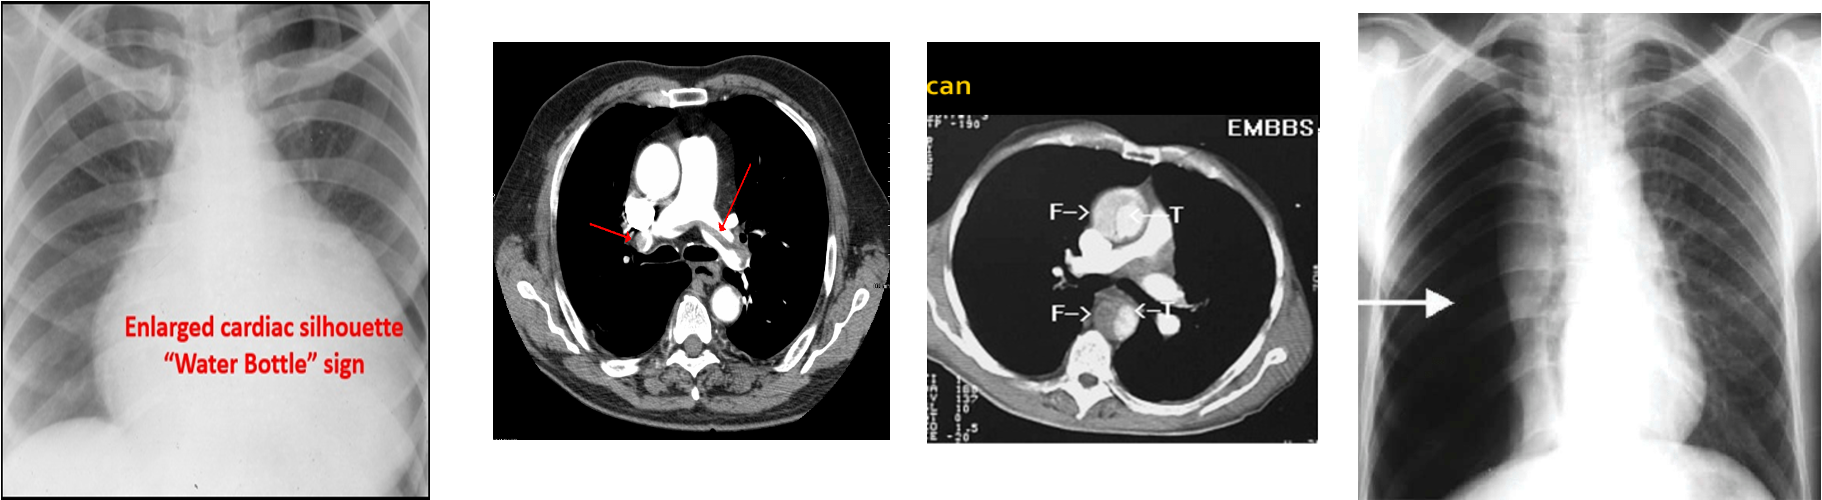

- CXR

Investigations